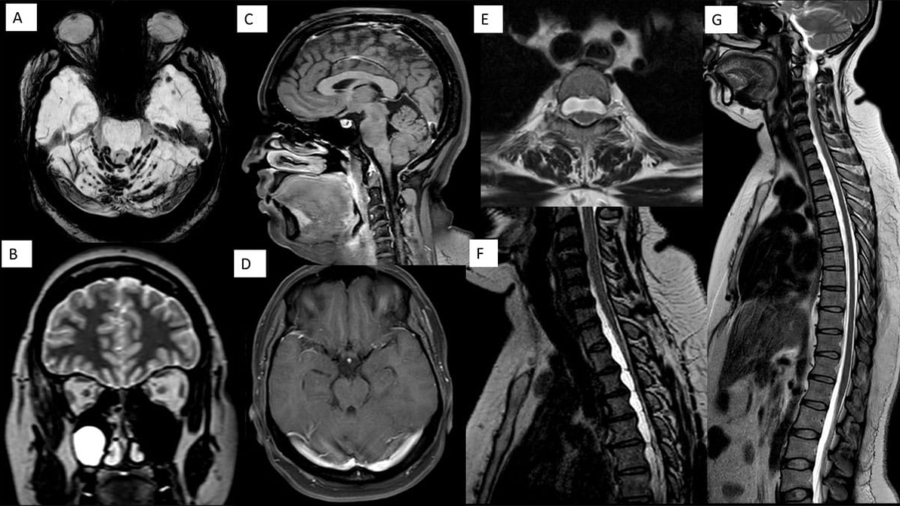

A 22-year-old male, born of nonconsanguineous parentage, presented with insidious onset, gradually progressive symmetrical upper limb and lower limb ataxia, dysarthria, and distal upper and lower limb weakness since the age of eight years.

June 2025